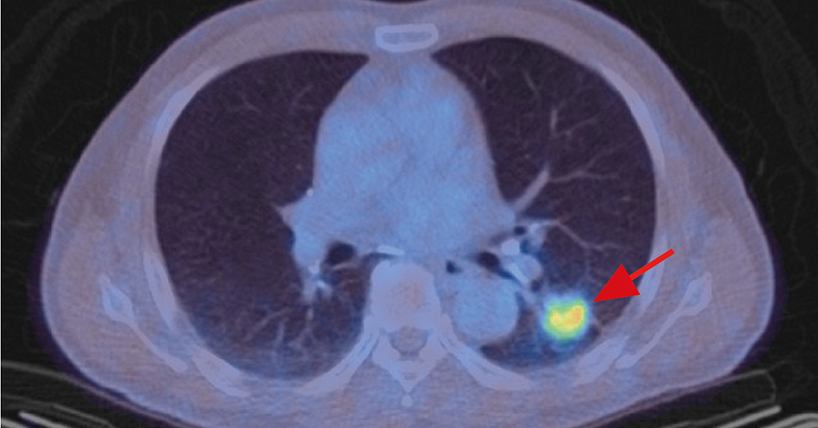

AIRIaL will develop medical imaging tests in the laboratory, that utilise artificial intelligence (AI) to automatically read lung scans, in order to develop new ways of predicting whether a cancer will respond to treatment.

As there is currently little understanding of how treatment resistance occurs in patients, this project will research new AI methods to automate the reading of medical images, to reliably identify the onset of therapy resistance over time.

The medical images will be acquired using next-generation molecular imaging probes developed by Dr Witney at King’s College London. Although this research will initially be performed in the laboratory using models of lung cancer, the researchers hope to be able to translate these findings into patient care in the future.